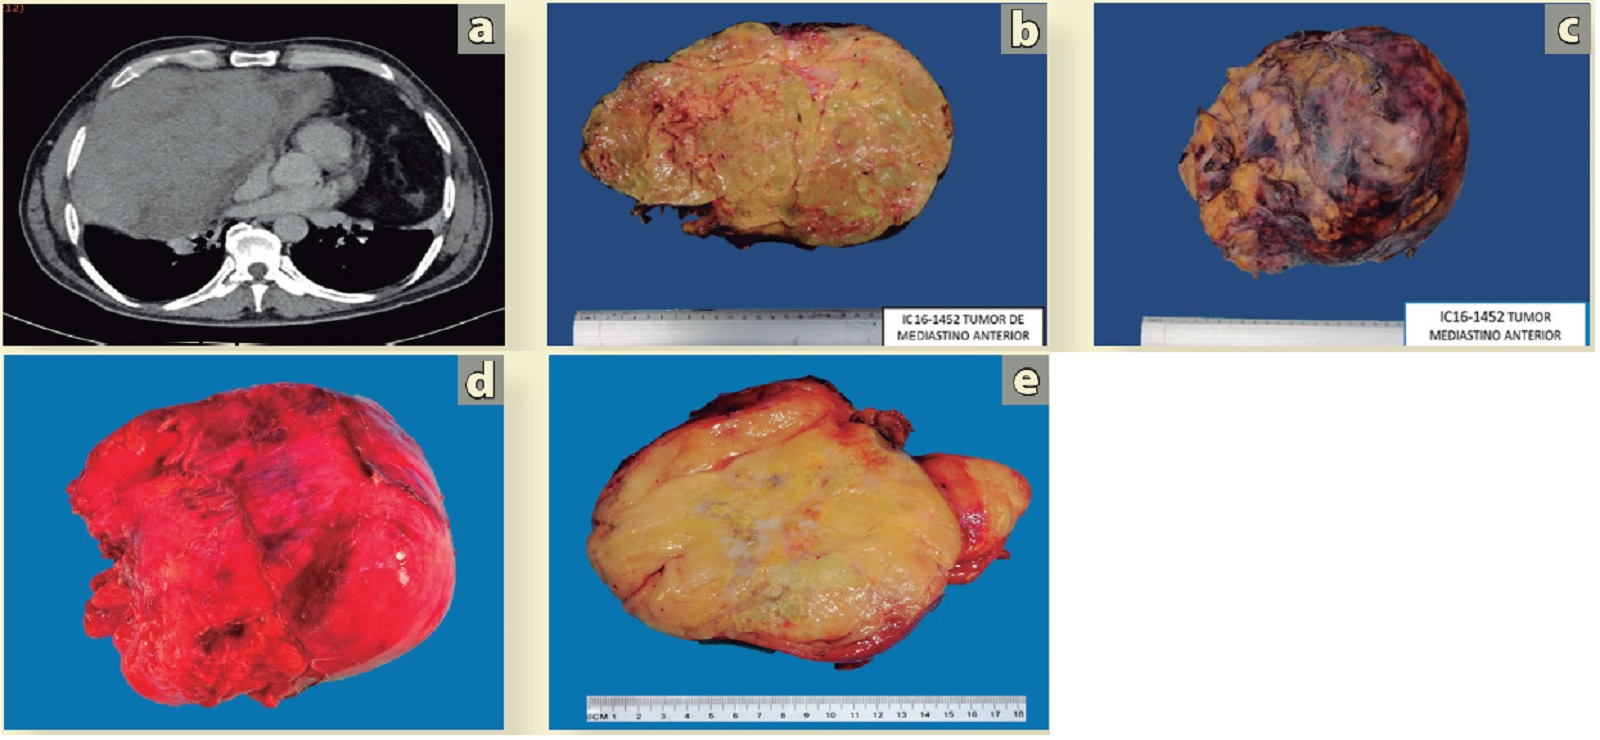

El paciente comentado en las Figuras 2 y 3 fue manejado con base en un diagnóstico de doble sarcoma primario de mediastino. Fue llevado a toracotomía secuencial, inicialmente con toracotomía posterolateral derecha con resección local amplia de un sarcoma fusocelular de alto grado y posteriormente a toracotomía posterolateral izquierda (a y b) con resección local amplia de un liposarcoma de bajo grado, c, d, e) El liposarcoma mediastinal anterior izquierdo (cabeza de flecha) sin infiltrar el parénquima pulmonar. El lóbulo pulmonar superior izquierdo se libera fácilmente mediante disección roma.

Figura 4 Toracotomía posterolateral Izquierda y resección local amplia de tumor de mediastino anterior.

a) El tumor desplaza, pero no infiltra el pulmón ni las estructuras del mediastino. b) Exéresis de la pieza quirúrgica, se observa un tumor de 20 X 12 cm; la superficie es lisa, bien definida, con reacción desmoplásica adyacente. c y d) La fotografía y el esquema muestran en la línea discontinua el cambio de un espacio virtual del mediastino a un espacio real, generado por el crecimiento lento y desplazante del tumor, que le permitió llegar a las dimensiones comentadas anteriormente.

Figura 5 Características morfológicas intraoperatorias del liposarcoma de bajo grado de mediastino.

b y с) Sarcoma fusocelular de alto grado, d y e) liposarcoma de bajo grado. Continuando la secuencia de análisis del caso de las figuras anteriores. a) En la tomografia, la densidad heterogénea y bordes irregulares de la lesión de la derecha (cabeza de flecha) se relacionan con el aspecto macroscópico característico del sarcoma fusocelular. Además, la flecha en la tomografia señala el aspecto homogéneo hipodenso de un liposarcoma en el lado izquierdo del mediastino, b) Superficie externa del tumor, bordes irregulares, amarilla opaca parcialmente cubierta de tejido adiposo, c) En la superficie de corte se observan áreas de necrosis, hemorrágicas y quísticas. d) Producto de la resección de tumor mediastinal izquierdo de 22 X 14 X 6 cm. La superficie externa del tumor luce congestiva, lisa, con bordes regulares, e) La pieza quirúrgica al corte es amarilla, lisa, brillante, es claro el aspecto lipomatoso del tumor.

Figura 6 Correlación imagenológica y aspecto macroscópico de un doble sarcoma de mediastino sincrónico.